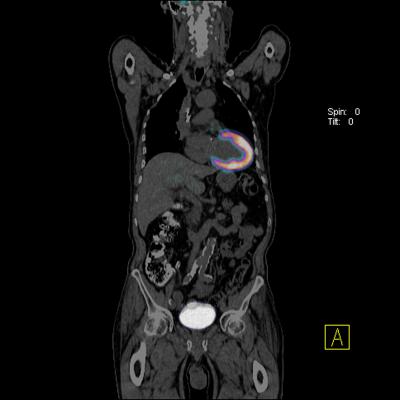

June 10, 2015 - In May, Group of Companies European Medical Center (GEMC) became the first private clinic in Russia to open a positron emission tomography (PET-CT) department producing its own pharmaceuticals. GEMC also opened a radiation cancer therapy department featuring two linear accelerators.

The Department of Radionuclide Diagnostics is equipped with PET-CT and Philips Gemini computed tomography (CT) systems and the single-photon emission computed tomography (SPECT) Philips Brightview XCT system. The department features a cyclotron by IBA that produces its own PET-CT radiopharmaceuticals. The extended quality control laboratory, equipped with the most modern equipment, is operational. A research technique on sentinel lymph node for breast cancer and melanoma is applied. An expansion of radiopharmaceutical production choline and tyrosine applied in oncourology and neurosurgery is planned in autumn 2015.